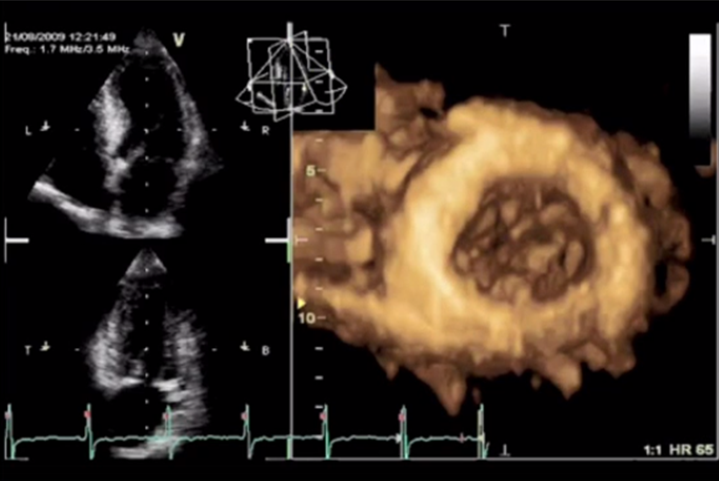

Методом выбора в оценке систолической функции миокарда является исследование фракций выброса левого желудочка при помощи эхокардиографии. Наилучшими являются измерения при помощи трехмерной эхокардиографии, а используемые иногда измерения в одномерном М-режиме по методу Тейхольца проводить нельзя, в связи с большим количеством неточностей и погрешностей. И при отсутствии трехмерной эхокардиографии исследование выполняется в двухмерном режиме по методу Симпсона.

Измерение ФВ ЛЖ в 2D режиме по Simpson

Измерение ФВ ЛЖ в 3D режиме

И разброс данных, получаемых при трехмерной эхокардиографии, даже у одного врача может составлять около 6%, а при двухмерной – около 10%.

Разница между измерениями в двухмерном и в трехмерном режимах может достигать 23%.

Стоит отметить, что положительной стороной исследования фракции с помощью эхокардиографии является ее доступность. Основные ее ограничения: от качества оборудования зависит качество изображения, имеет значение и опыт врача. Поэтому для серийной оценки фракции выброса левого желудочка необходимо использовать одно и то же оборудование, а измерения, желательно, чтобы выполнял один и тот же врач.